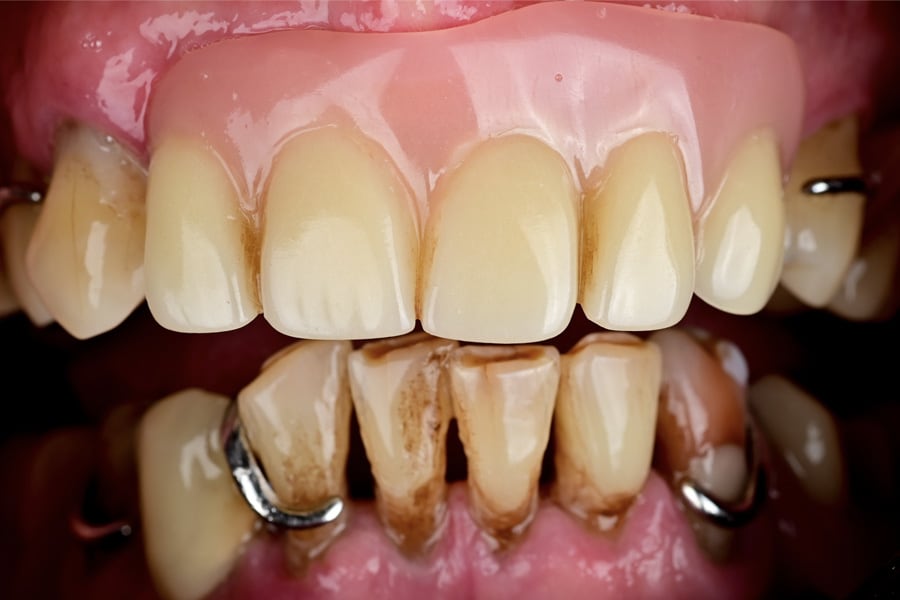

A 62-year-old male patient presented with severely compromised dentition in both jaws, marked by advanced periodontal breakdown, missing posterior teeth, and failing prosthetic restorations (Figure 1 through Figure 3). The patient expressed dissatisfaction with esthetics, difficulty in mastication, and poor confidence in social settings. After medical history review, no contraindications for implant therapy were identified. The patient requested fixed restorations with minimal invasiveness and rapid functional recovery.

During surgery, flapless osteotomies were prepared under guided conditions. All implants achieved insertion torque values sufficient for immediate loading. Multi-unit abutments were connected, and the PMMA provisionals were relined intraorally, ensuring passive seating. Occlusion was carefully adjusted to light centric contacts and shallow lateral guidance, minimizing overload during early osseointegration (Figure 18 and Figure 19).